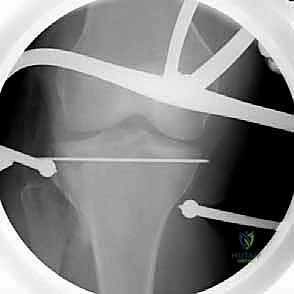

التدخل الجراحي (ORIF): خطوة بخطوة مع الأستاذ الدكتور محمد هطيف

التثبيت الداخلي المفتوح (Open Reduction and Internal Fixation - ORIF) هو الإجراء الجراحي القياسي لكسور الهضبة الظنبوبية الجانبية المزاحة. بفضل خبرته الواسعة وتدريبه المتقدم، يُجري الدكتور هطيف هذه العمليات بدقة متناهية.

5. رد الكسر ورفع الانخساف (Reduction & Elevation)

هذه هي الخطوة الأكثر دقة. يقوم الدكتور هطيف بفتح نافذة صغيرة في عظم الساق أسفل الكسر، ويستخدم أدوات خاصة لدفع العظم المفصلي المنهار إلى الأعلى حتى يعود إلى مستواه الطبيعي تماماً، ليطابق الهضبة الإنسية.

7. التثبيت النهائي بالشرائح والمسامير (Plating)

بعد التأكد من استواء السطح المفصلي بواسطة الأشعة داخل العمليات (C-arm)، يتم تثبيت العظم باستخدام شريحة معدنية تشريحية ذات مسامير مغلقة (Locking Compression Plate - LCP). هذه الشرائح الحديثة تعمل كـ "دعامات داخلية" توفر ثباتاً استثنائياً، وتسمح للمريض ببدء تحريك ركبته في اليوم التالي للجراحة.